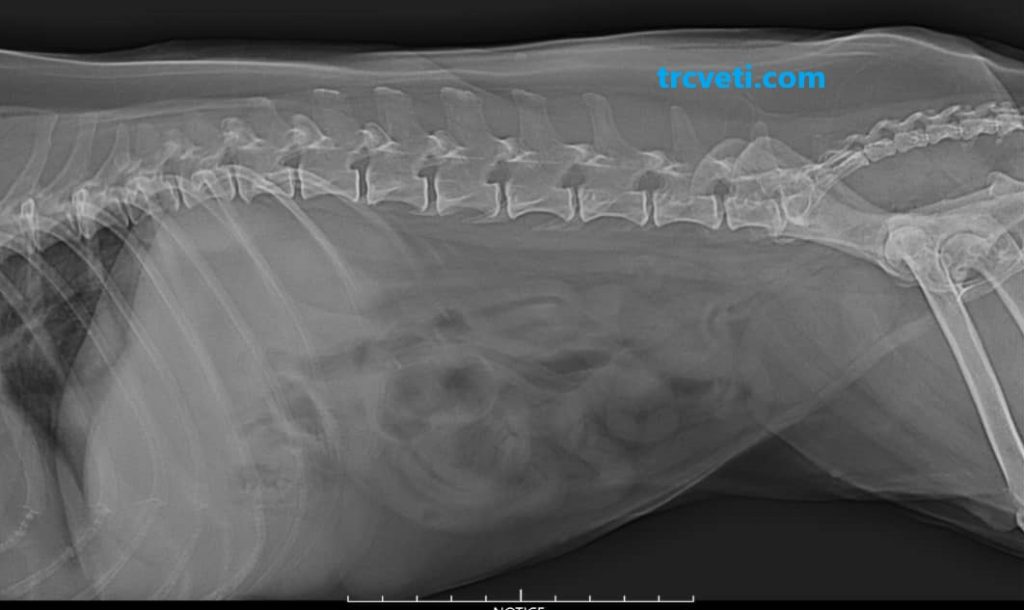

Images: The radiographic study includes abdominal and pelvic views, as well as lateral and VD views of the knee joints. The quality of the radiographs is satisfactory.

Abdominal Radiographs:

– The kidneys appear smaller than normal and are not well visualized.

– Normal radiographic appearance of the stomach, bowels, urinary bladder, and other abdominal organs.

– No other radiographic abnormalities are detected.

Lumbar Vertebrae:

Note: lumbar vertebrae are included and there is evidence of generalized osteopenia. The spondylosis deformans is seen between L7 and sacrum.